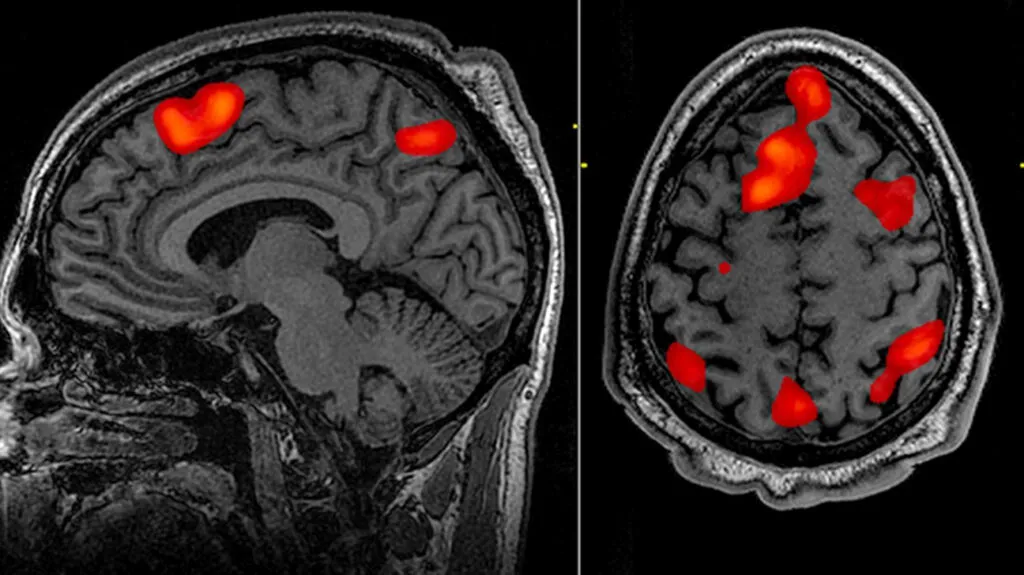

Η μελέτη, που δημοσιεύτηκε στο περιοδικό PNAS Nexus, είναι η μεγαλύτερη μέχρι σήμερα μελέτη που χρησιμοποιεί σαρώσεις εγκεφάλου με λειτουργική μαγνητική τομογραφία (fMRI) για τη μελέτη της πολιτικής ιδεολογίας.

Είναι επίσης μια από τις λίγες μελέτες που εξέτασαν τη λειτουργική συνδεσιμότητα σε σχέση με την ιδεολογία, μια προσέγγιση ολόκληρου του εγκεφάλου που εξέτασε ποια μέρη του εγκεφάλου έχουν δείξει παρόμοια μοτίβα δραστηριότητας κατά την εκτέλεση συγκεκριμένων εργασιών, υποδεικνύοντας ότι επικοινωνούν μεταξύ τους.

«Κοιτάξαμε τον εγκέφαλο ως ένα σύνθετο σύστημα περιοχών που αλληλεπιδρούν μεταξύ τους για να παράγουν αυτές τις συμπεριφορές. Οι περισσότερες άλλες μελέτες εξέτασαν μια περιοχή του εγκεφάλου σε απομόνωση για να δουν αν ενεργοποιήθηκε ή όχι όταν υποβλήθηκε σε πολιτικά ερεθίσματα», είπε Skyler Cranmer ένας εκ των συμμετεχόντων στην έρευνα .

Αυτή η μελέτη έδειξε ότι οι ενεργοποιήσεις συγκεκριμένων περιοχών του εγκεφάλου, της αμυγδαλής, της κατώτερης μετωπιαίας έλικας και του ιππόκαμπου, συνδέονταν πιο έντονα με τις πολιτικές δεσμεύσεις.